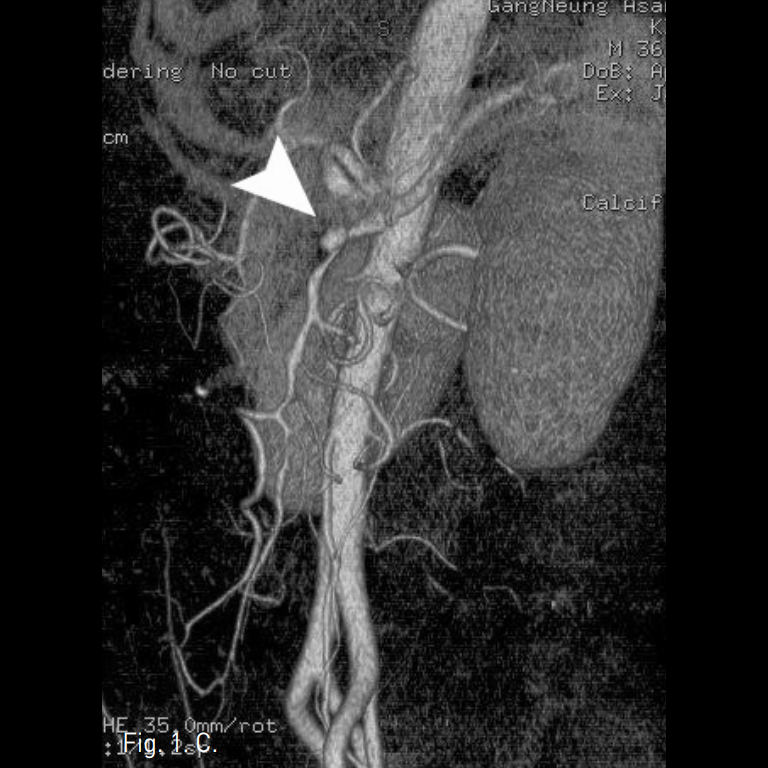

시술 전 CTA상 상장간막동맥 근위부에 직경 10mm 크기의 박리성동맥류가 확인되었고, 상장간막동맥은 벽내혈종으로 인해 혈관 직경은 12mm로 커지고 내강은 3mm로 협착소견을 보였다(Fig. 1A-C).

Fig. 1

A-C. Initial CT scan (A) shows dilated SMA with circumferential intramural hematoma and stenotic true lumen (arrow). Sagittal reconstructed MIP image (B) and volume rendered 3D CTA (C) show 1cm sized dissecting aneurysm (arrow hed) at proximal SMA and diffuse narrowing of true lumen.